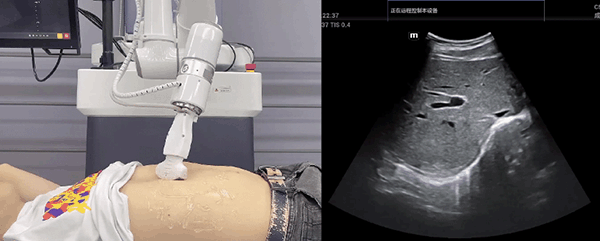

星空xk机器人末端搭载超声探头,可以对浅表小器官和外周血管、腹部(肝、胆、胰、肾等器官)进行超声检查。

目前,星空xk机器人在生物医药、医疗健康领域的赋能已有显著进展,星空xk协作机器人应用场景覆盖了临床试验、试管检测、拭子采集、试管搬运、荧光检测、康复治疗、超声扫查、导诊、消毒、微创治疗、针灸刮痧等。